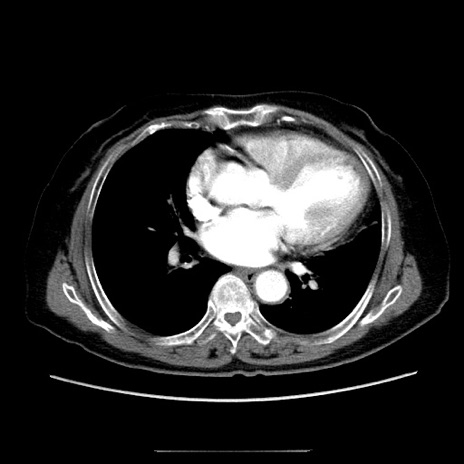

症例5(横断像)

【症例】70歳代女性

【主訴】お腹が張る

【現病歴】1週間くらい前から腹部膨満の自覚あり。昨日夜から増悪したため、本日救急外来受診。

【身体所見】意識清明、BT 36.5℃、BP 165/106mmHg、HR 80bpm、SpO2 98%、腹部:膨満、軟、自発痛・圧痛なし、触診にて不快感あり、腸蠕動音:減弱

【データ】WBC 12600、CRP 1.04